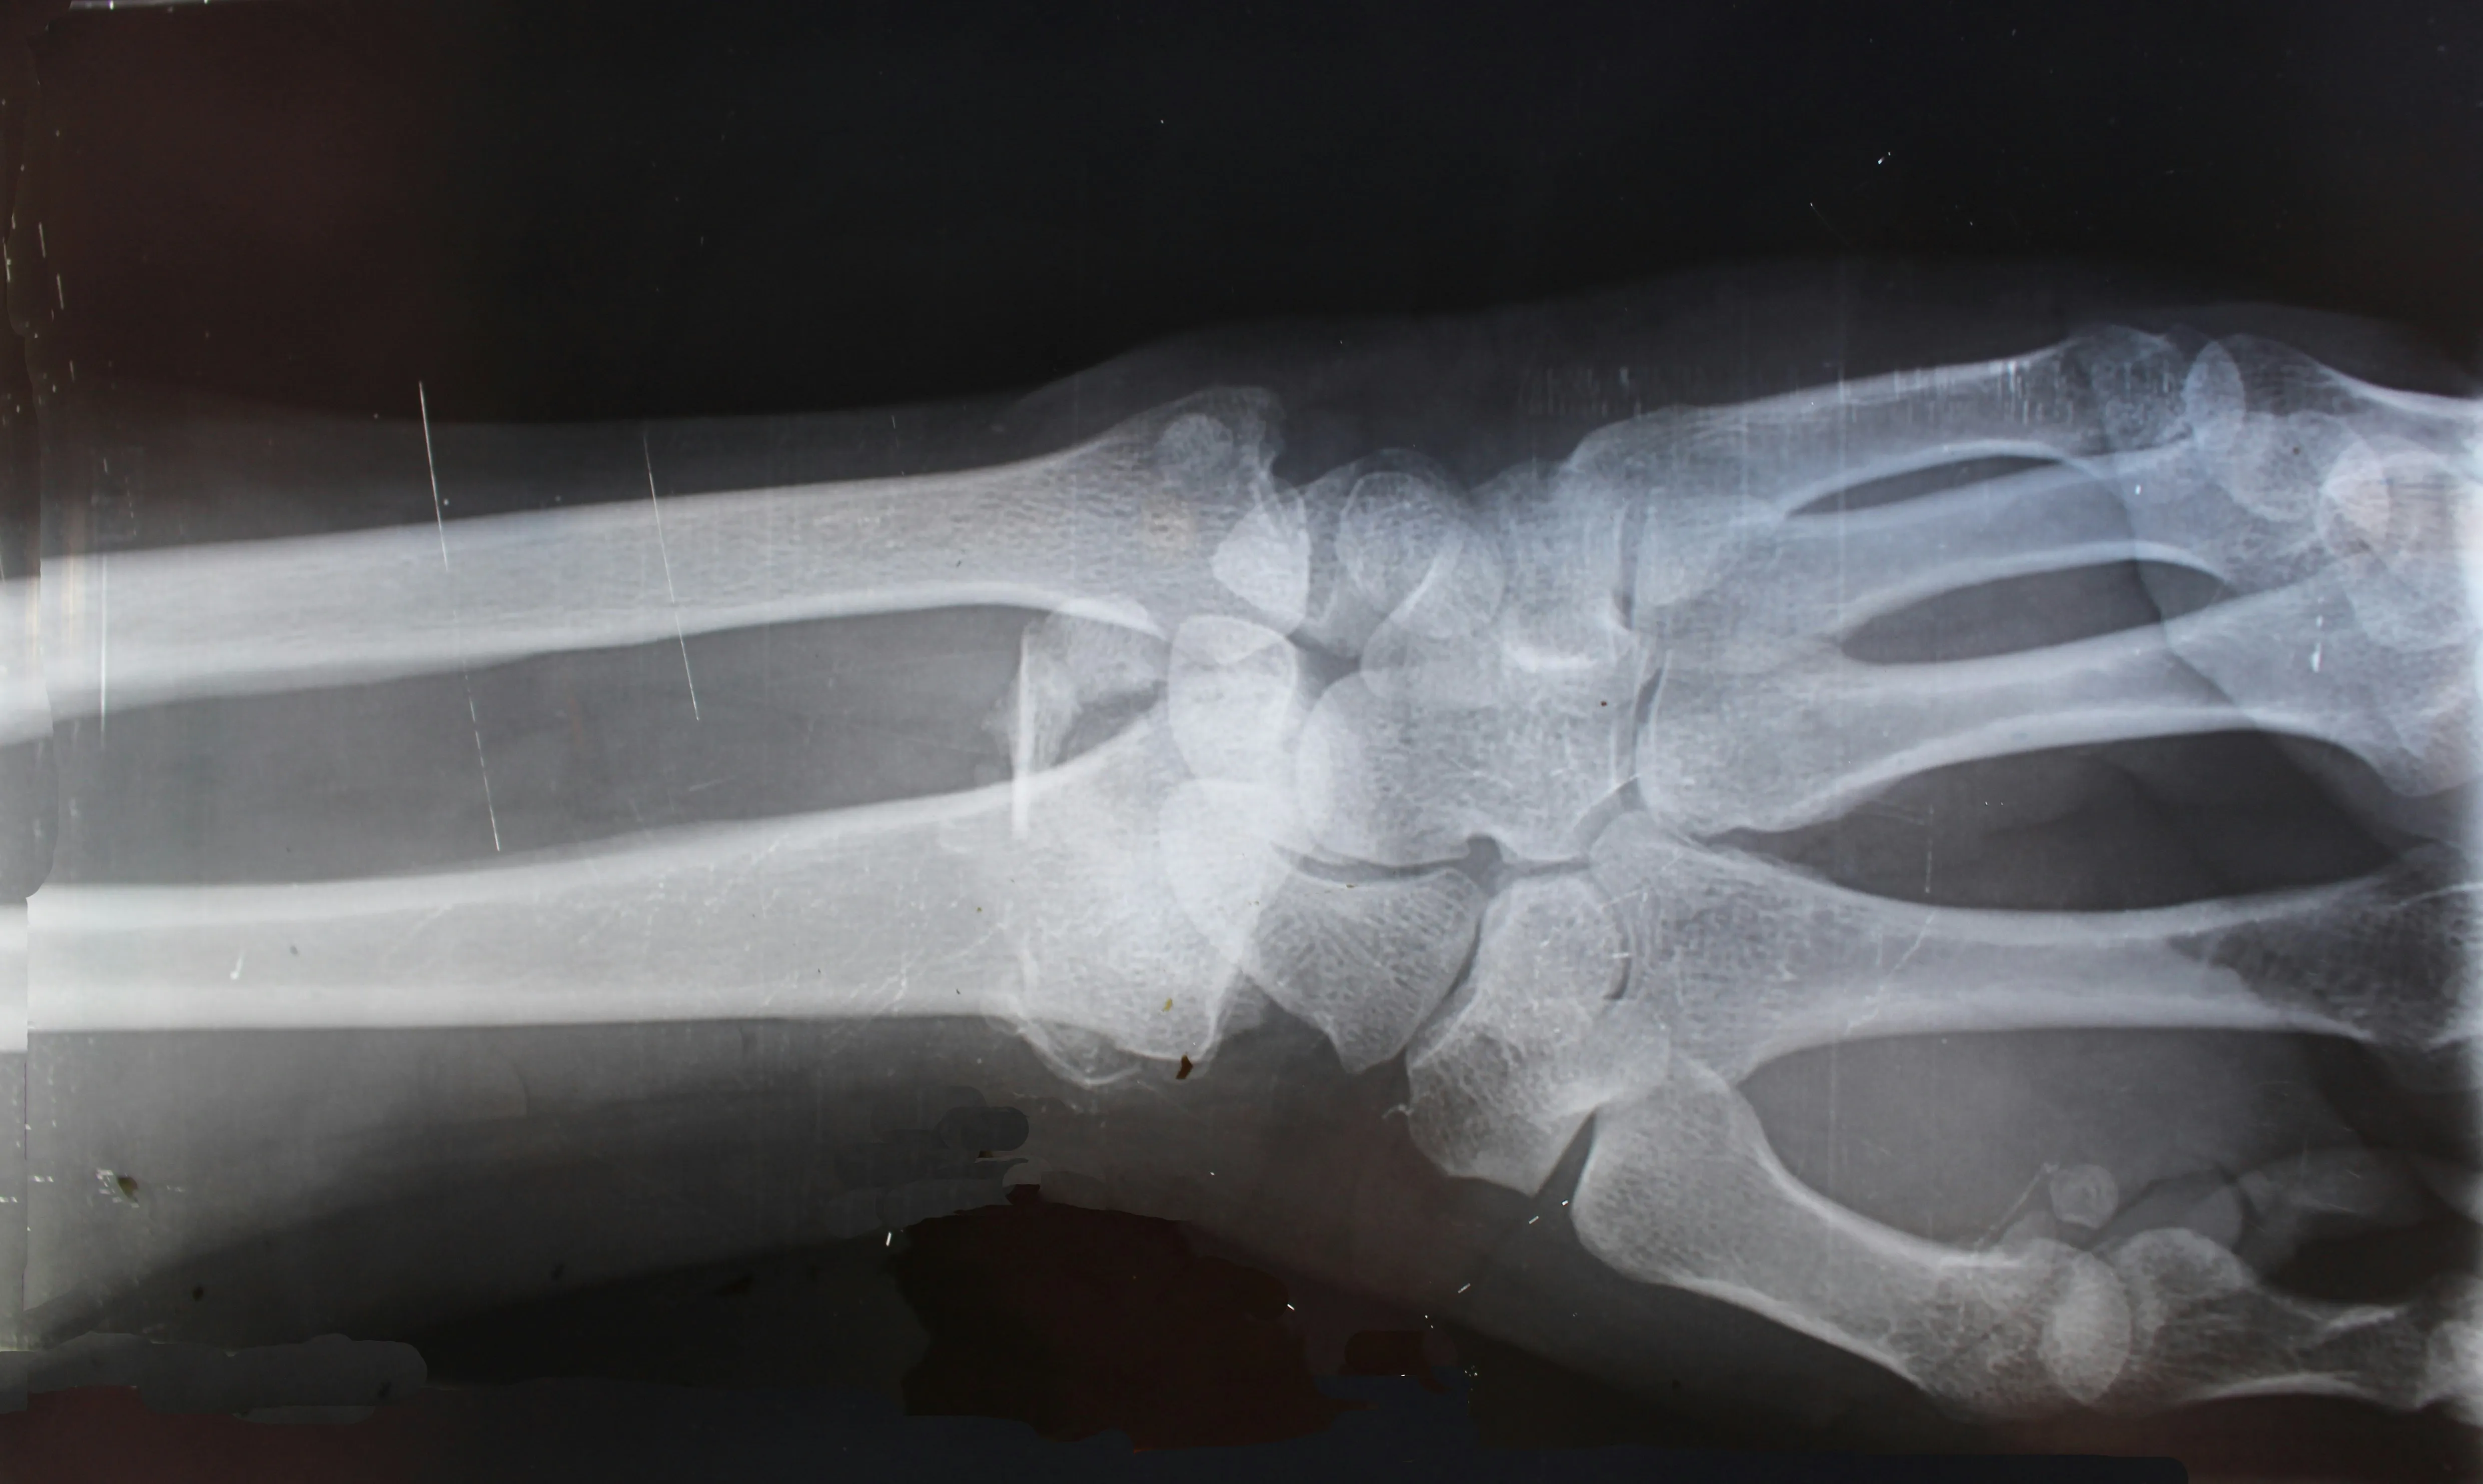

Detailed wrist X-ray showing bone structure

Detailed X-ray film showing bone structure